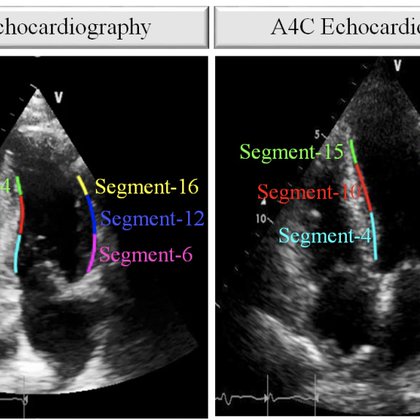

New Torrent! HMC-QU echocardiography ultrasound recordings (Dataset)

academictorrents.com

The HMC-QU benchmark dataset is created by the collaboration between Hamad Medical Corporation (HMC), Tampere University, and Qatar University. The usage of data has been approved by the local ethics...